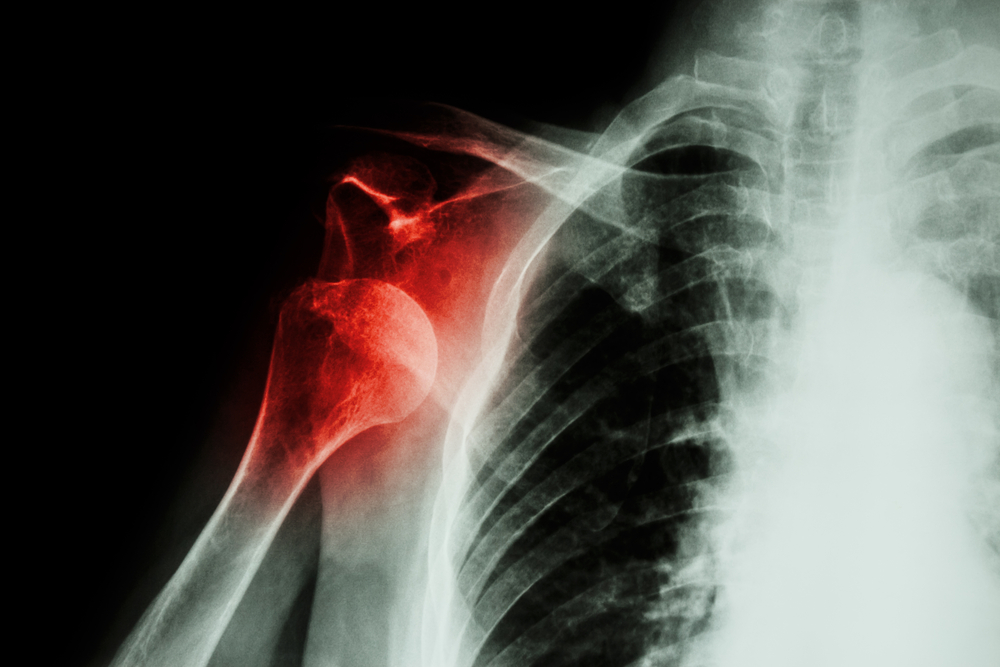

Dislocation:A dislocation is the movement of a bone at a joint from its normal position. When the bone is moved out of place, the joint no longer functions. Usually, dislocations happen at the shoulder, elbow, wrist, jaw and hip. Sprain / Strain:A sprain is the tearing of the ligaments at a joint. Sprains mostly occur at the ankle, knee, wrist and fingers. A strain is the stretching and tearing of a muscle. They usually occur in the neck, back, thigh, or the back of the lower leg. Use RICE method when dealing with a sprain or strain:

A dislocation is the movement of a bone at a joint from its normal position. When the bone is moved out of place, the joint no longer functions. Usually, dislocations happen at the shoulder, elbow, wrist, jaw and hip.